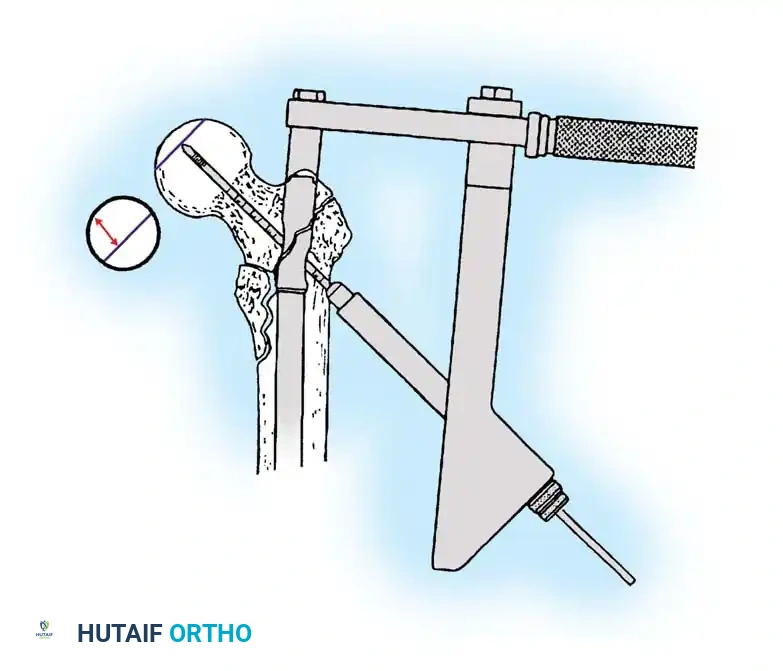

1. Patient Positioning and Reduction

The patient is placed supine on a radiolucent fracture table. The operative leg is secured in a traction boot, and the well leg is placed in a hemilithotomy position or scissored posteriorly to allow unobstructed access for the C-arm fluoroscope.

Proper patient positioning on the fracture table is paramount. Ensure the C-arm can freely rotate from AP to lateral without obstruction.

Closed Reduction Maneuver:

1. Apply longitudinal traction to restore leg length.

2. Internally rotate the leg (typically 10 to 15 degrees) to correct the external rotation deformity and bring the femoral neck parallel to the floor.

3. Verify reduction on both AP and lateral fluoroscopic views. An acceptable reduction must have cortical apposition medially and anteriorly.

3. Guide Wire Placement

Whether using an SHS or a CMN, accurate placement of the guide wire into the femoral head is the most critical step of the operation.

Insertion of the guide wire. The wire must be positioned centrally in the femoral head on both AP and lateral views.